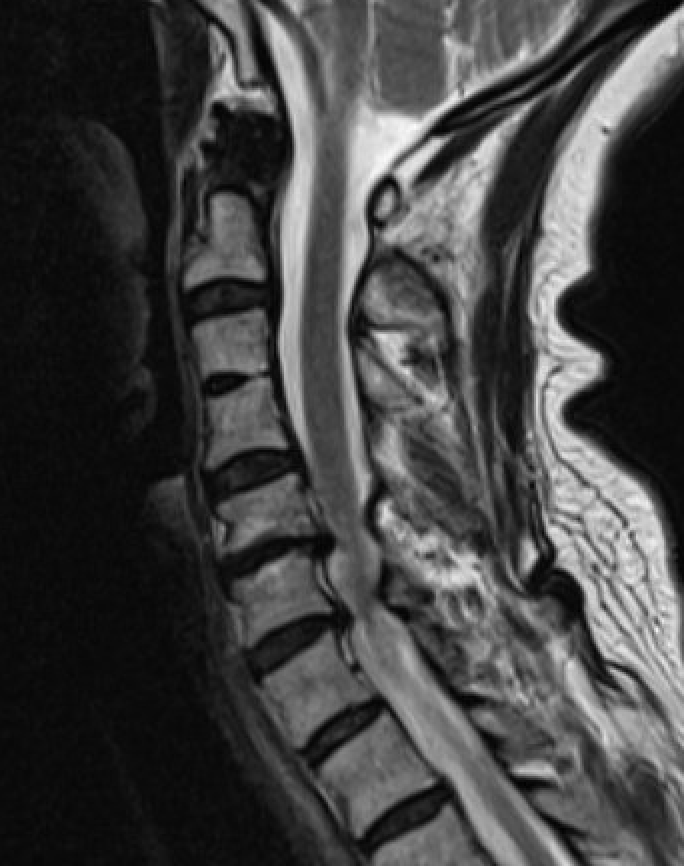

MRI

Degenerative disc changes

- dessication (loss of fluid)

- narrowing

- end plate changes

End plate changes Disc dessication with disc bulge